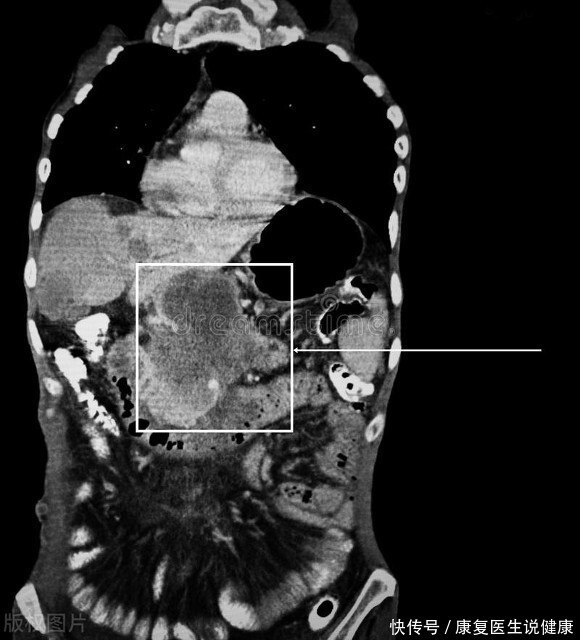

这4种癌症藏得很深,发现时大多数是晚期,切记别忽略这些信号

肝癌

胃癌

胰腺癌

原发性肝癌